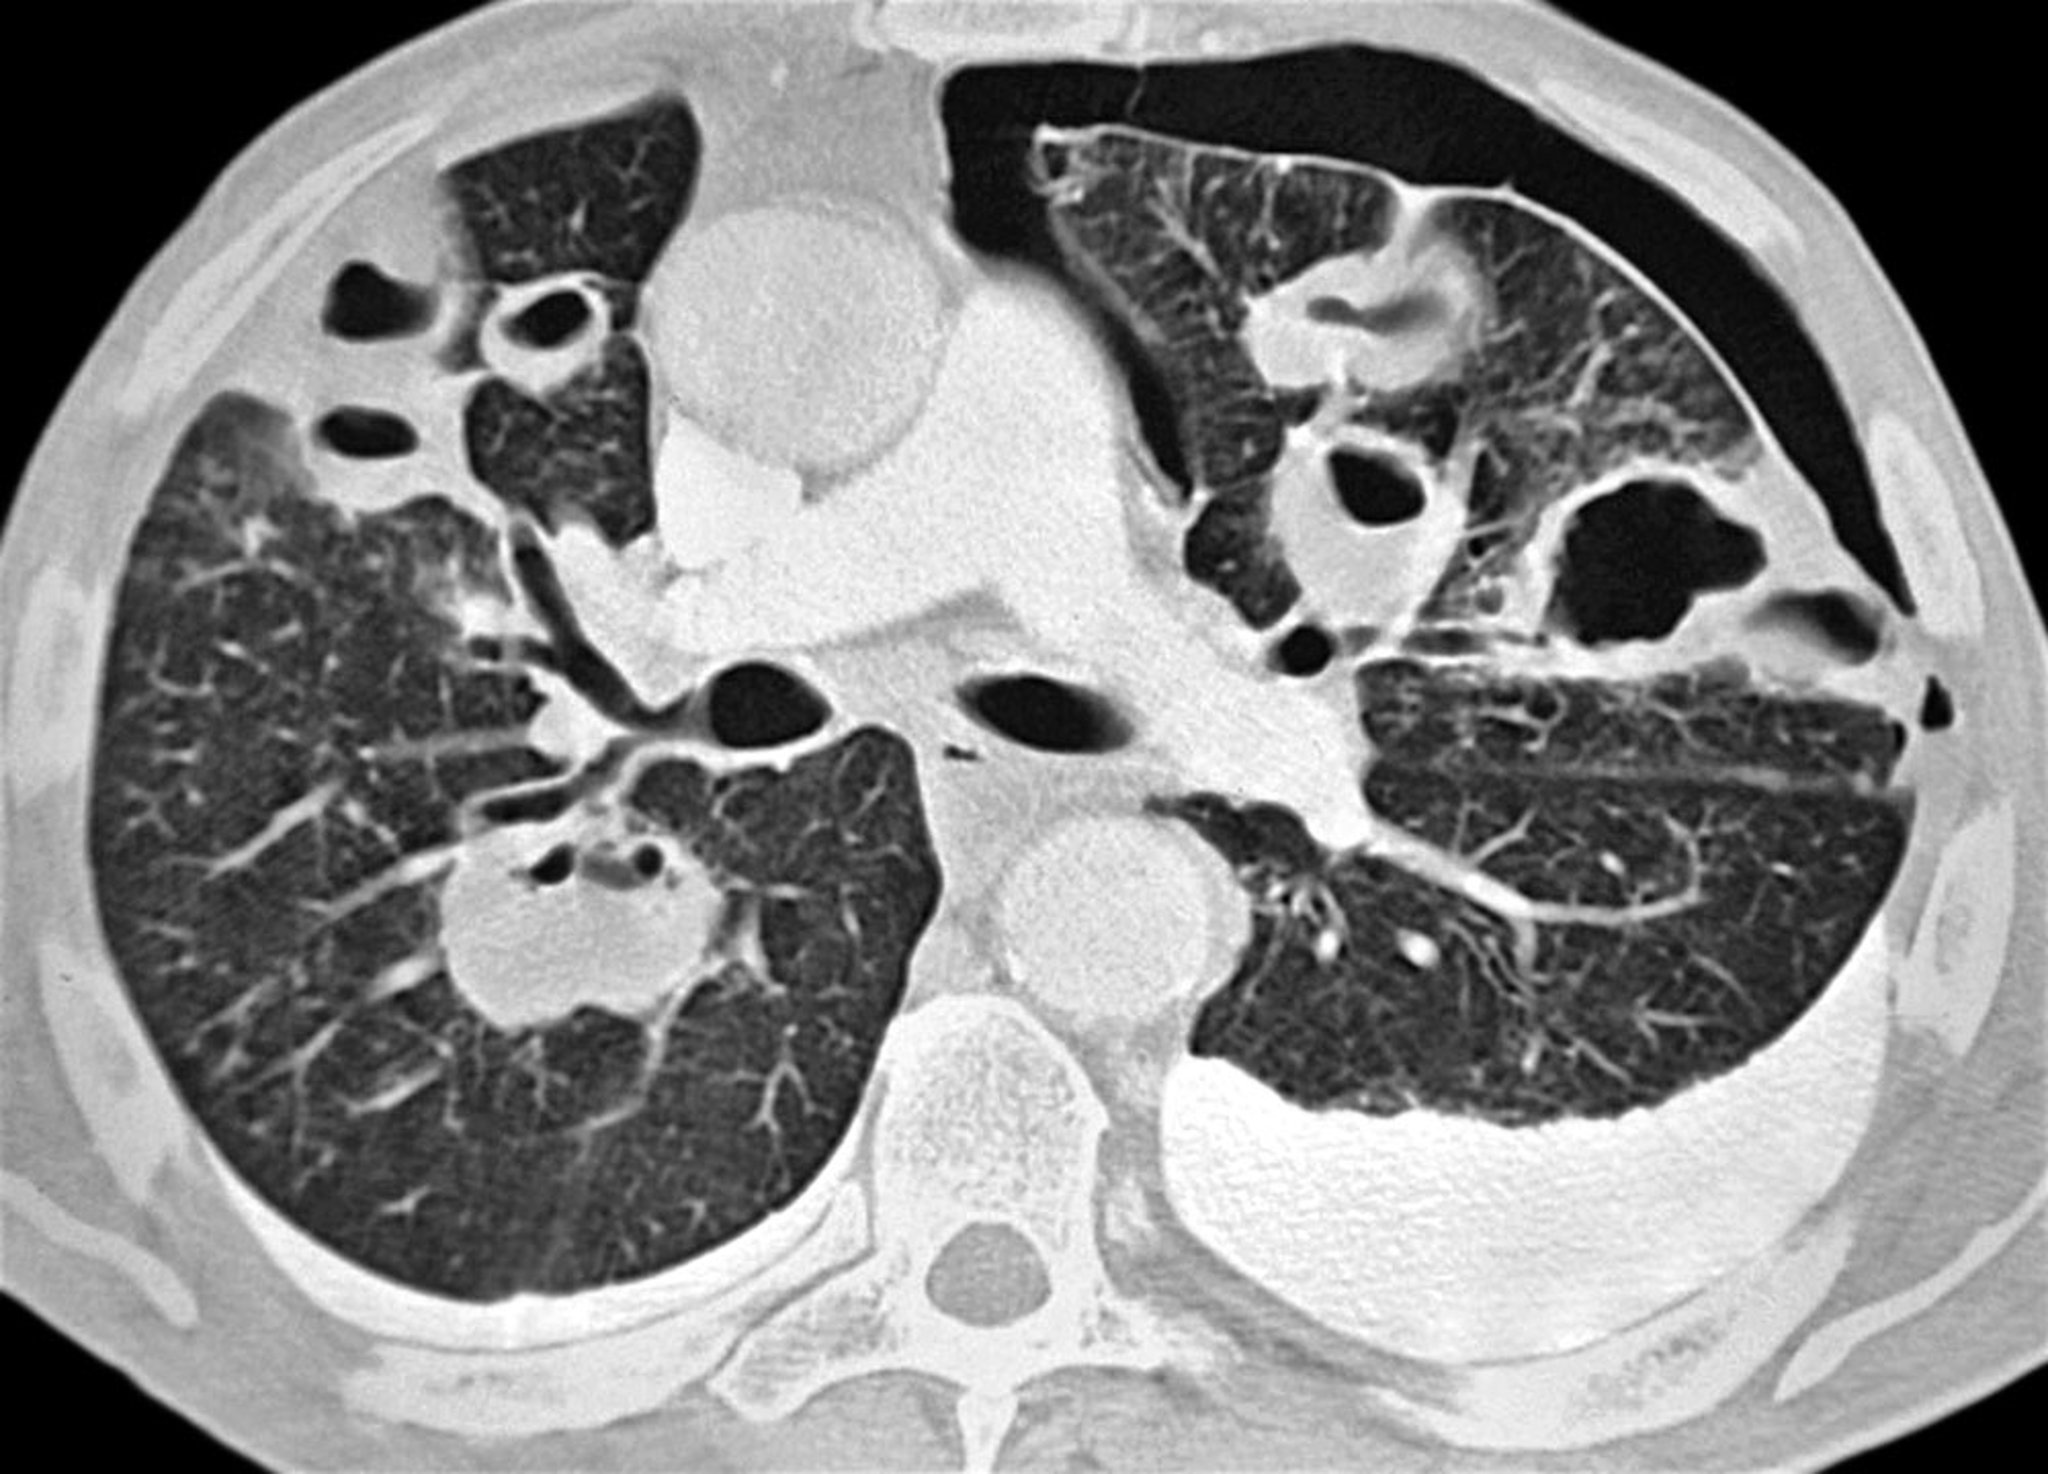

Chẩn đoán này được nghi ngờ ở những bệnh nhân có tình trạng ổn định nhưng bị khó thở hoặc đau ngực kiểu màng phổi và thường được xác nhận bằng chụp X-quang ngực tư thế thẳng đứng. Mật độ mô phổi tăng lên nếu chụp phim phổi khi thở ra, do đó làm tăng sự khác biệt về độ tương phản giữa không khí trong khoang màng phổi và mô phổi liền kề (có ít không khí hơn do sự kết hợp của trạng thái thở ra và bất kỳ tình trạng xẹp phổi nào). Viền khí không cản quang và không có vân phổi giữa phổi hoặc thùy phổi với màng phổi lá thành là dấu hiệu củan tràn khí màng phổi. Di lệch khí quản và dịch chuyển trung thất được quan sát thấy trong tràn khí màng phổi nhiều. Chẩn đoán cũng có thể được đưa ra bằng siêu âm tại giường nếu bệnh nền ở phổi không ngăn cản việc quan sát đầy đủ.

Tràn khí màng phổi ít (ví dụ: < 10%) đôi khi bị bỏ qua trên phim chụp X-quang ngực. Ở những bệnh nhân có khả năng bị tràn khí màng phổi, cần theo dõi vân phổi đến tận mép màng phổi trên phim chụp X-quang ngực. Ngay cả tràn khí màng phổi lớn cũng có thể không thấy rõ trên phim chụp X-quang tư thế nằm ngửa và cần đặc biệt chú ý đến dấu hiệu rãnh sâu (góc sườn hoành sâu bất thường) vì đây có thể là dấu hiệu duy nhất của tràn khí màng phổi trên phim chụp X-quang ở bệnh nhân nằm ngửa. Các tình trạng giống tràn khí màng phổi trên chẩn đoán hình ảnh bao gồm khí phế thũng, nếp gấp da, tấm trải giường gấp và chồng lên nhau của dạ dày hoặc ruột trên vùng phổi.

Chụp CT cũng cho phép hiển thị hình ảnh rõ ràng của tràn khí màng phổi và các bệnh lý liên quan ở bệnh nhân nằm ngửa.